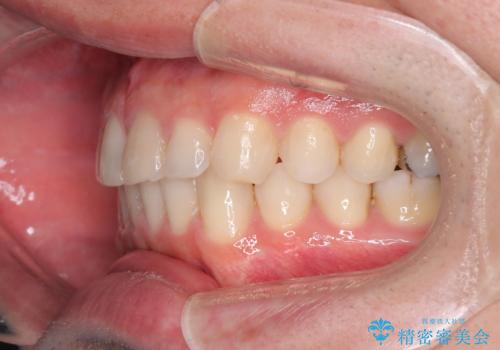

- 前歯の隙間と歯のデコボコを主訴にご来院された患者様です。

加えて、上下の奥歯が全く咬み合わないシザーズバイトの状態も認められました。

矯正検査の結果、非抜歯でインビザラインによる治療が可能と判断し、治療を行いました。

歯の隙間とデコボコ、シザーズバイトも改善され、咬み合わせや見た目が整い、患者様にも大変ご満足いただけました。